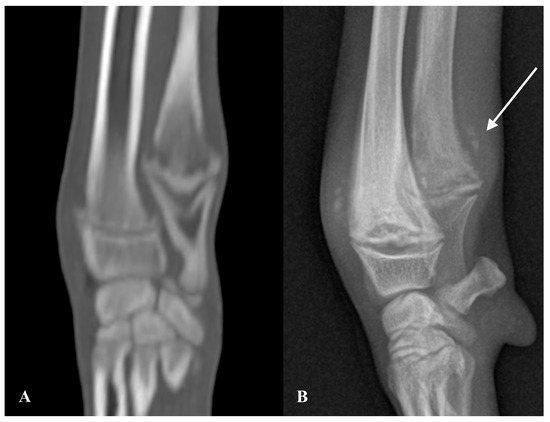

Radiographs of the left humerus and bilateral carpi and tarsi revealed an irregular, radiolucent metaphyseal line parallel to the physis within the proximal humerus, and distal radius, ulna, and tibia bilaterally, creating a “double physis sign” (Figure 2B). Mild-to-moderate sclerosis was present adjacent to the radiolucent metaphyseal lines. New bone formation separated from the cortex was present around the affected metaphyses of the radius, ulna, and tibia, consistent with metaphyseal paracortical cuffing, and moderate soft tissue swelling centred on the metaphyses was also noted (Figure 2B).

Due to the potential need for follow-up imaging, orthogonal radiographs of both distal forelimbs, both stifles, and a mediolateral view of the right shoulder were obtained (Figure 3B). An irregular, radiolucent metaphyseal band parallel to the physis was observed within the proximal right humerus, bilateral distal femur, radius and ulna, and bilateral proximal tibia. Moderate sclerosis of the adjacent metaphyseal bone was present, along with a faint, solid periosteal reaction at the caudal aspect of the proximal right humeral metaphysis. The radiographic findings supported the presumed diagnosis of MO.

Figure 2. Case 1. Sagittal Multiplanar Reconstruction (MPR) image with bone algorithm of the distal antebrachium on CT at presentation (A) and mediolateral radiographic view of the distal antebrachium one month after presentation (B). A thin irregular hypoattenuating metaphyseal band is present in the distal radius and ulna, the changes are more severe in the ulna at presentation and mild in the radius (A). In the radiograph (B), the radiolucent band is associated with adjacent bone sclerosis and mild new bone formation is present cranial to the radius and caudal to the ulna, suspected to represent paracortical cuff (white arrow). Moderate soft tissue swelling centred at the metaphyseal region can also be noted in (B).